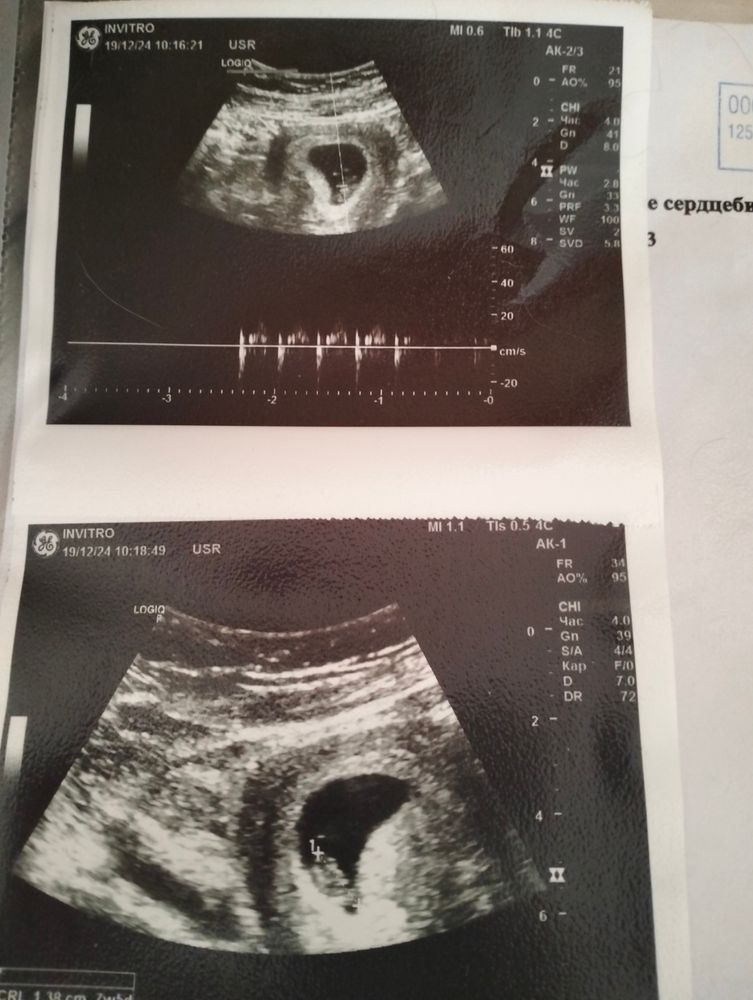

Девочки, поделитесь, пожалуйста, вашим опытом - кто сталкивался с гипертонусом? У нас 8 недель, неделю назад перенервничала из-за мужа, решила сегодня проверить на УЗИ, все ли ок. Нашли гипертонус + деформацию плодного яйца(говорят, это не страшно и проходит с тонусом, не беспокоиться на счёт этого). Кто сталкивался? Вредит ли это малышу и как быстро проходит?